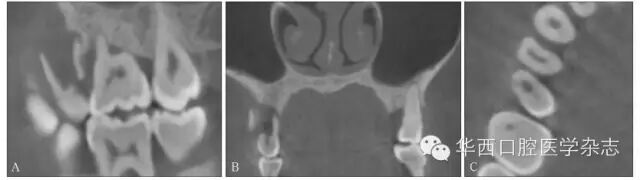

ABCBCT矢状位、冠状位见15牙根折裂,冠状位见根管壁较对侧同名牙变薄,折片向颊侧移位,C:轴位见15牙颊侧根管内径扩大,提示有内吸收。

9 内吸收导致根折裂

3.3.2 与牙内吸收鉴别根折裂轴位可见颊舌向贯通的折线,根管壁不连续;内吸收则是根管内径的局部扩大,根管壁连续性未中断(图9)。